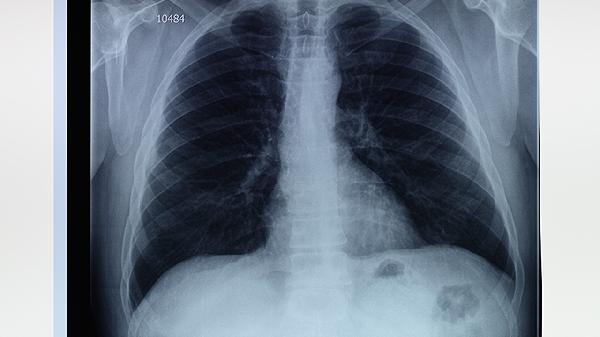

肺氣腫肺大泡可通過藥物治療、氧療、肺康復訓練、手術治療、生活方式調整等方式治療。肺氣腫肺大泡通常由長期吸煙、空氣污染、遺傳因素、慢性支氣管炎、職業(yè)粉塵接觸等原因引起。

肺氣腫的初期癥狀主要有活動后氣短、慢性咳嗽、胸悶、乏力。 1、活動后氣短 早期肺氣腫患者在爬樓梯或快步行走時可能...